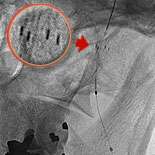

Fig 4: A stent, which is a metallic cage, is placed in the artery to keep it opened.

The cutting edge treatment is to insert a carotid filter balloon which is an umbrella like device used to catch debris as the artery is being opened. Fig.1 shows Ralph's narrowing of the left carotid artery. Fig.2 shows the device being inserted in Ralph's artery. In fig.3 the carotid balloon's up showing inflation of the balloon which opens the blocked artery. A stent (fig.4) which is a metallic cage is placed in the artery to keep it opened.